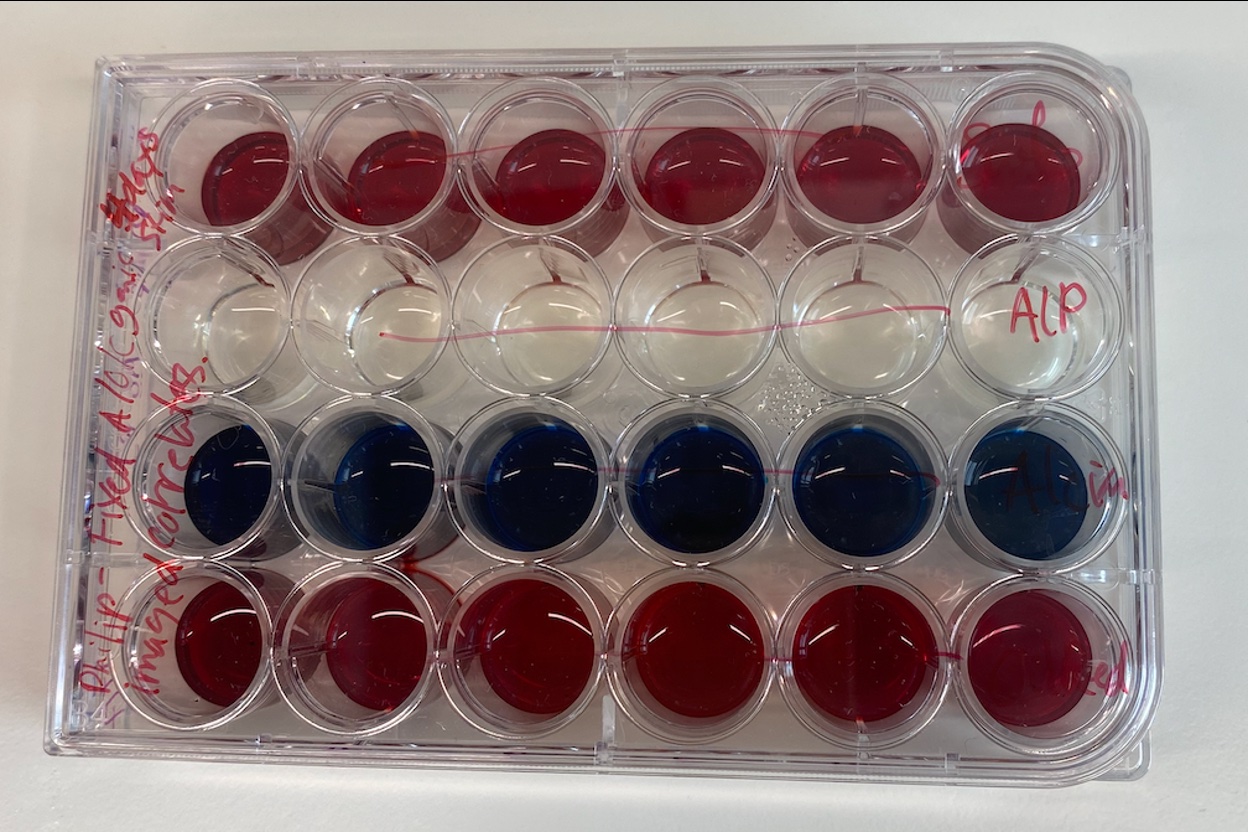

24-well plate: Alcian blue, oil red, ALP, Alizarin Red. Assessing differentiation of hMSCs.

24-well plate: Alcian blue, oil red, ALP, Alizarin Red. Assessing differentiation of hMSCs.